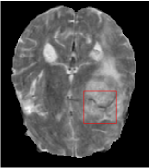

All the experiments are implemented on a Windows workstation with Intel Core i9 CPU at 3.3GHz and an Nvidia GTX-1080Ti GPU with 11GB of graphics card memory via TensorFlow Abadi et al. (2016). The parameters in the proposed network are initialized by using Xavier initialization Glorot and Bengio (2010). We trained the meta-learning network with four tasks synergistically associated with four different CS ratios: 10%, 20%, 30%, and 40%, and test the well-trained model on the testing dataset with the same masks of these four ratios. We have 300 training data for each CS ratio, which amount to total of 1200 images in the training dataset. The results for and MR reconstructions are shown in Tables 5.4 and 5.4 respectively. The associated reconstructed images are displayed in Figures 1 and 3. We also test the well-trained meta-learning model on unseen tasks with radio masks for skewed ratios: 15%, 25%, 35%, and random Cartesian masks with ratios 10%, 20%, 30% and 40%. The task-specific parameter for the unseen tasks are retrained for different masks with different sampling ratios individually with fixed task-invariant parameters . In this experiments, we only need to learn for three skewed CS ratios with radio mask and four regular CS ratios with Cartesian masks. The experimental training proceed on less data and iterations, where we performed on 100 MR images with 50 epochs. For example, for reconstructing MR images with CS ratio 15% radio mask, we fix the parameter and retrain the task-specific parameter on 100 raw data with 50 epochs, then test with renewed on our testing data set with raw measurement that sampled from radio mask with CS ratio 15%. The results associated with radio masks are shown in Table 5.4 and 5.4, Figure 2 and 4 for and images respectively. The results associated with Cartesian masks are list in Table 5.4 and reconstructed images are displayed in Figure 5.

In this section, we test the generalizability of the proposed model that tests on unseen tasks. We fix the well-trained task-invariant parameter and only train for sampling ratios 15%, 25% and 35% with radio masks and sampling ratios 10%, 20%, 30% and 40% with Cartesian masks. In this experiment, we only used 100 training data for each CS ratio and apply a total of 50 epochs. The averaged evaluation values and standard deviations are listed in Table 5.4 and 5.4 for reconstructed T1 and T2 brain images respectively that proceed with radio masks, and Table 5.4 shows the qualitative performance for reconstructed T2 brain image that applied random Cartesian sampling masks. In T1 image reconstruction results, meta-learning improved 1.6921 dB in PSNR for 15% CS ratio, 1.6608 dB for 25% CS ratio, and 0.5764 dB for 35% comparing to the conventional method, which in the tendency that the level of reconstruction quality for lower CS ratios improved more than higher CS ratios. A similar trend happens in T2 reconstruction results with different sampling masks. The qualitative comparisons are illustrated in Figure 2, 4 and 5 for T1 and T2 images tested in skewed CS ratios in radio masks, and T2 images tested in Cartesian masks with regular CS ratios respectively. In the experiments that conducted with radio masks, meta-learning is superior to conventional learning especially at CS ratio 15%, one can observe that the detailed region in red boxes keeps edges and is more close to the true image, while conventional method reconstructions are hazier and lost details in some complicated tissue. The point-wise error map also indicates that Meta-learning has the ability to suppress noises.